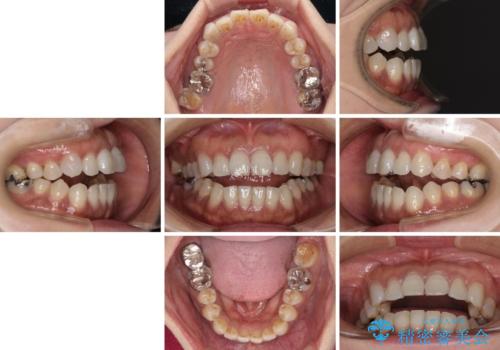

極端な上下前歯の開咬を改善 オープンバイトのインビザライン矯正

- 上下前歯の隙間を気にして来院された患者様です。

開咬の治療は、前歯を閉じるように動かすとともに、上下臼歯を圧下(骨内にめり込ませる)させることで進めて行きます。

インビザラインは臼歯の圧下を効果的に行えるため、インビザラインを用いて矯正治療を行うこととしました。

治療前に、いくらインビザライン矯正がオープンバイトを得意としているとは言え、さすがに限界があるだろうと思っておりましたが、前歯でレタスが噛めるまで改善することができました。

顔の印象も大きく変わり、患者様には大変満足していただきました。